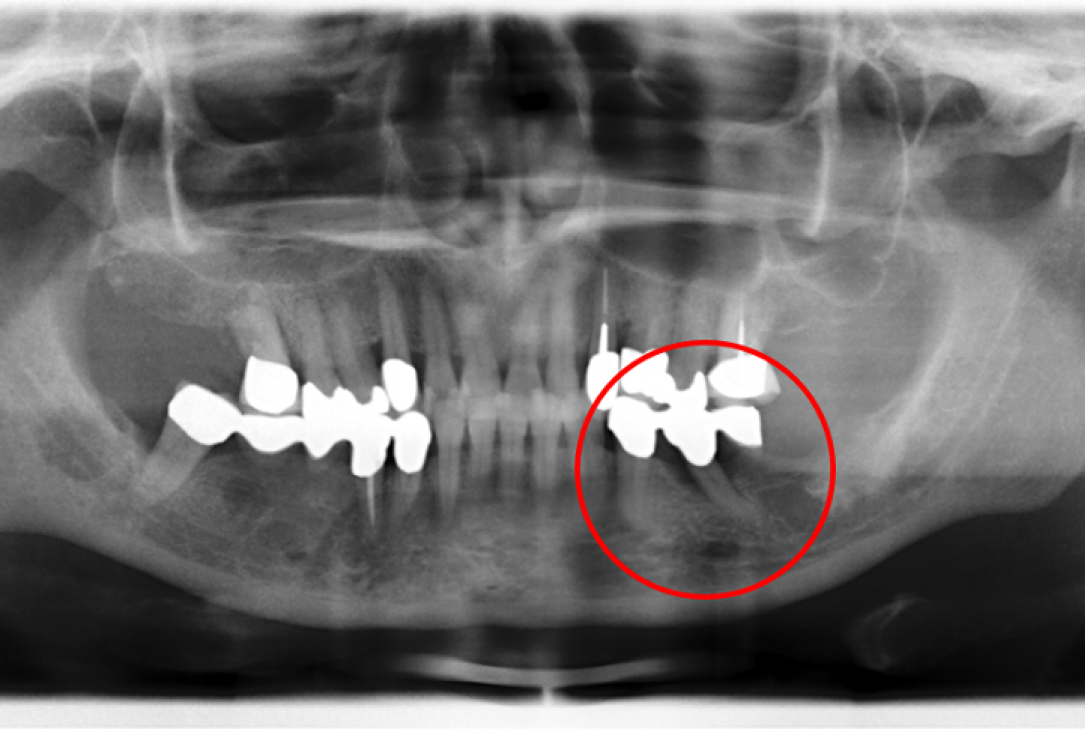

01/02 - Radiographic view before periodontal regenerative therapy with Straumann® Emdogain®. A deep intrabony defect appeared mesially and distally on the left mandibular first premolar. Pre-surgical probing measured 8 mm. The defect morphology presented as well-contained.Contained intrabony defect treated using Straumann® Emdogain® - Prof. Dr. Dr. A. Kasaj